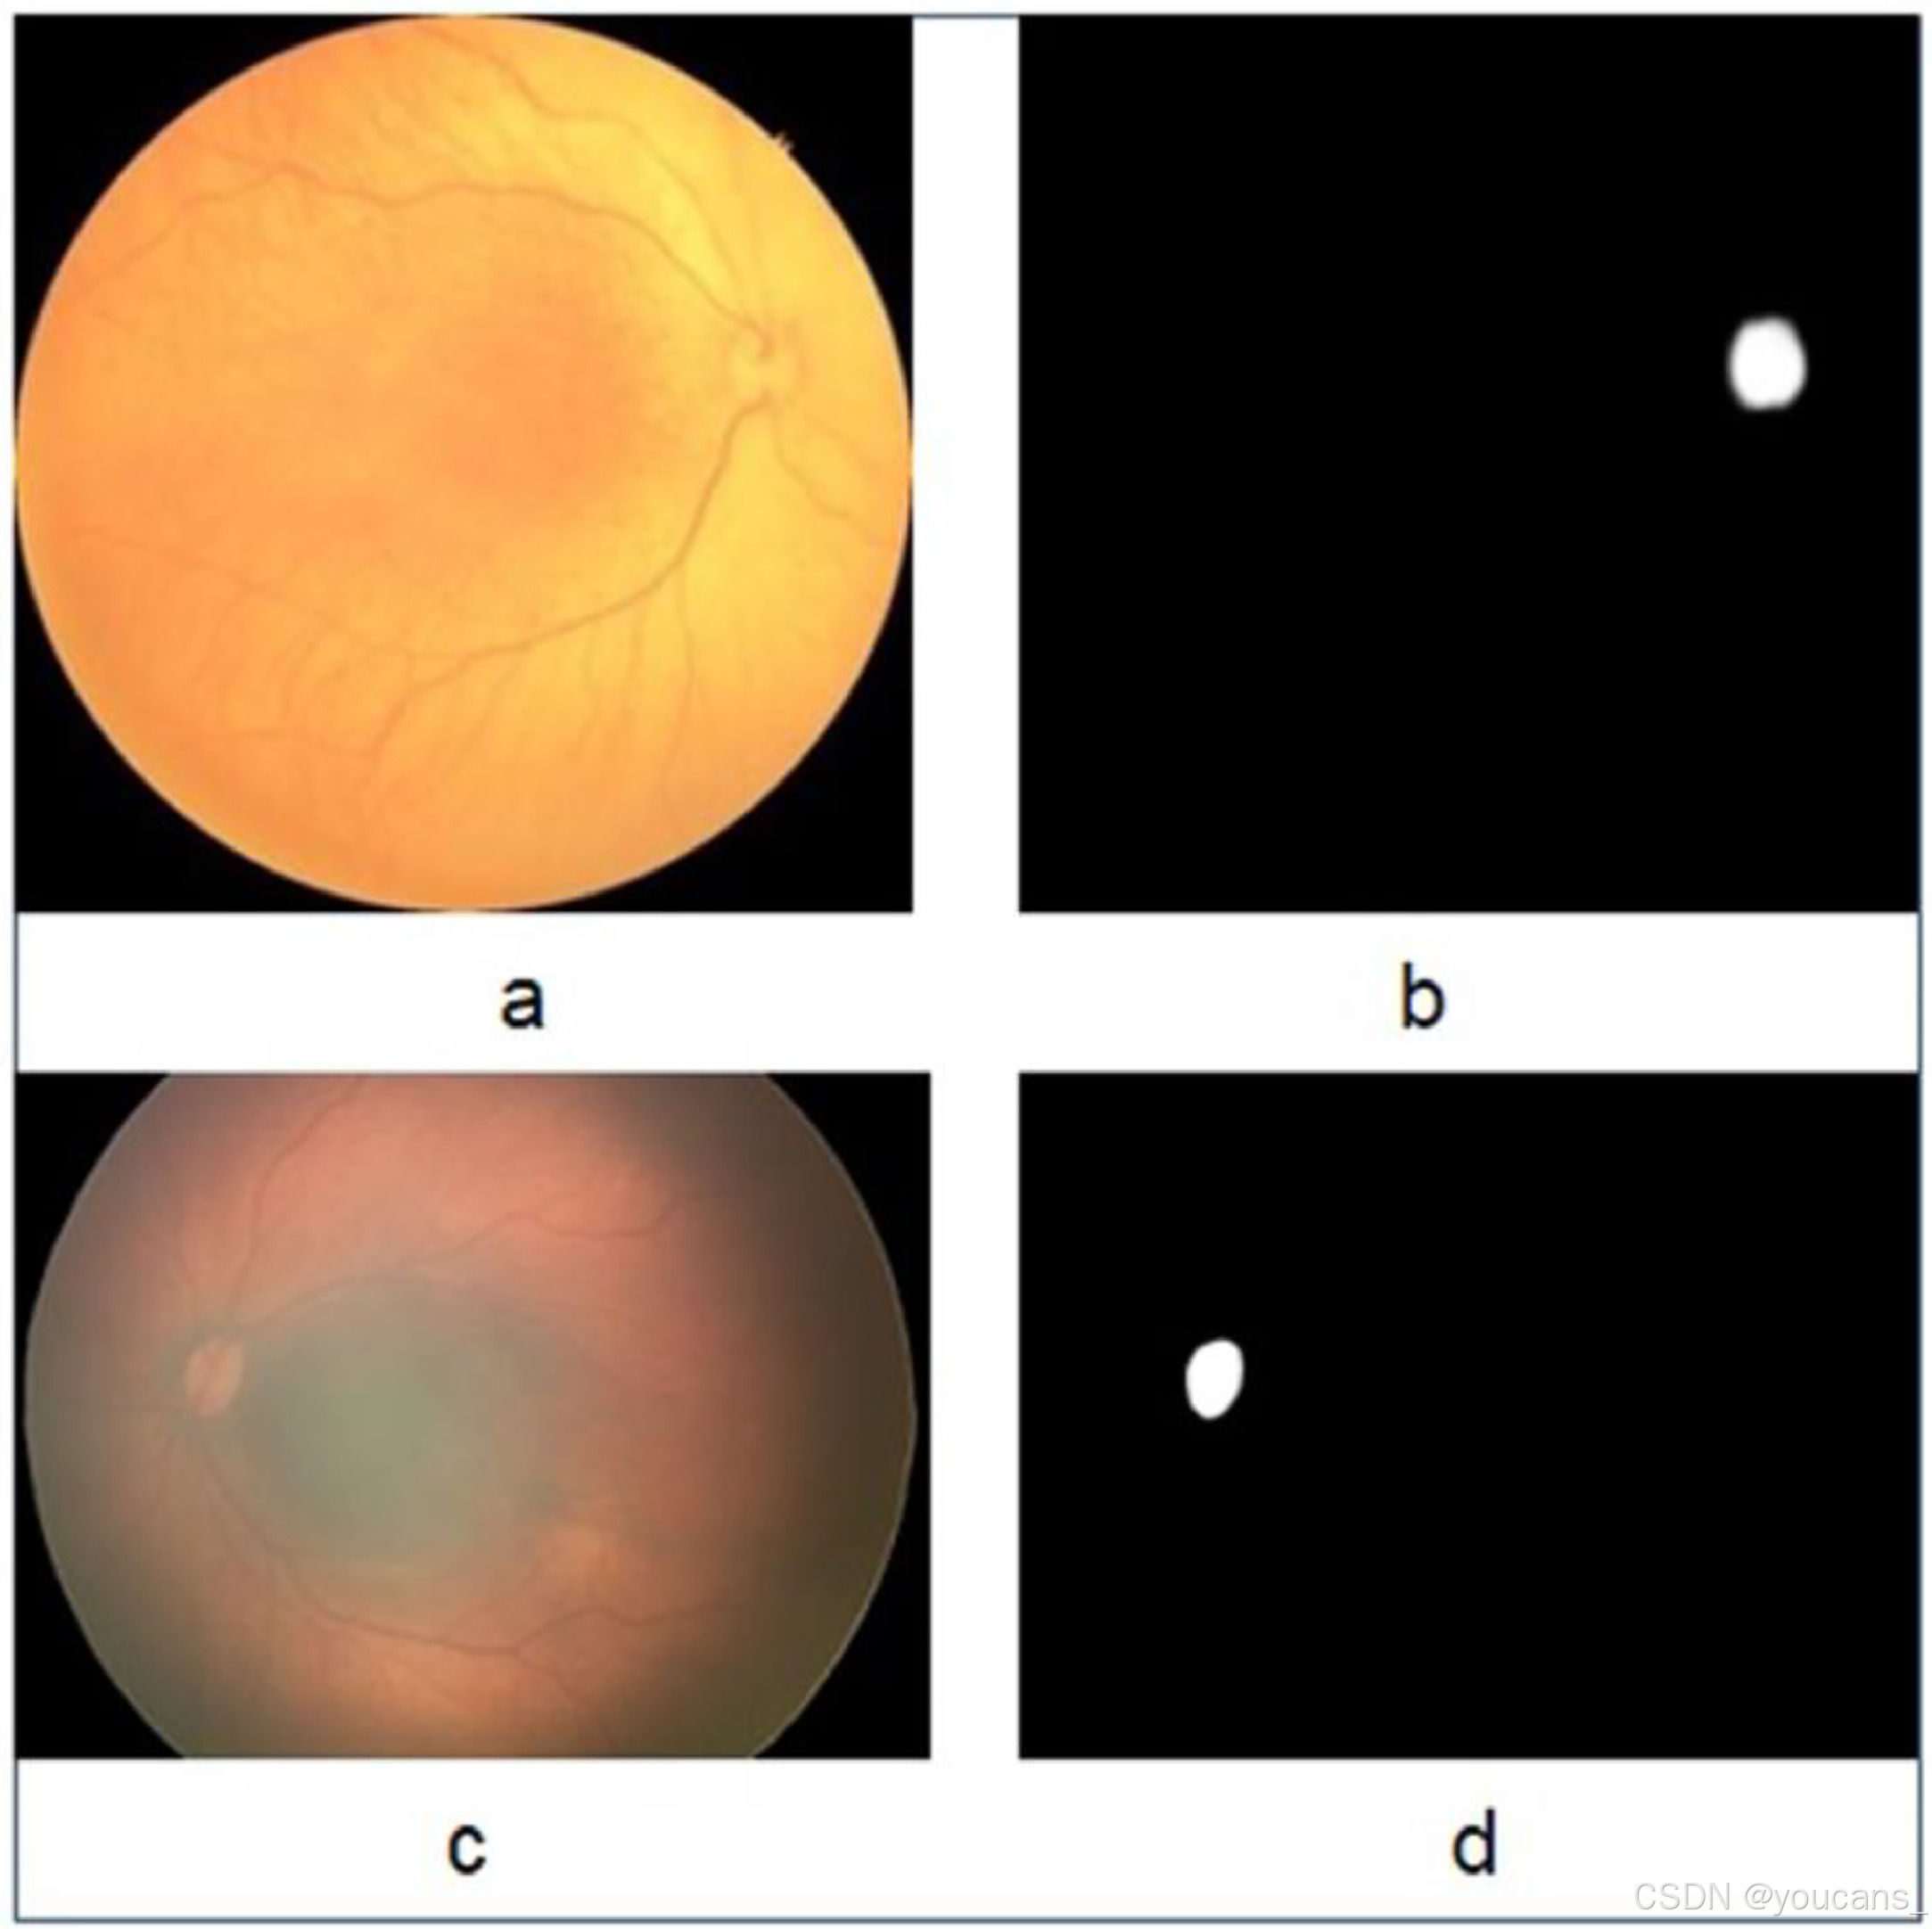

3.3 视盘分割图像

视神经盘(Optic Disc)是眼底图像中重要的解剖结构,通过后部视图获取。分割的掩模图像是使用Adobe Photoshop Reader手动创建的,如图4 所示。

HVDROPDB-OD 数据集 用于视盘的分割,包含以下子集:

- RetCam_OpticDisc_images,通过 RetCam 成像系统捕获的视盘图像。

- RetCam_OpticDisc_masks,与 RetCam 对应的视盘掩模图像。

- Neo_OpticDisc_images,通过 Neo 成像系统 捕获的视盘图像。

- Neo_OptictDisc_mask,与 Neo 对应的视盘掩模图像。

图4:用于视盘分割的原始图像和掩模图像:(a)Neo 原始图像,(b)Neo 掩模图像,(c)RetCam 原始图像,(d)RetCam 掩模图像。